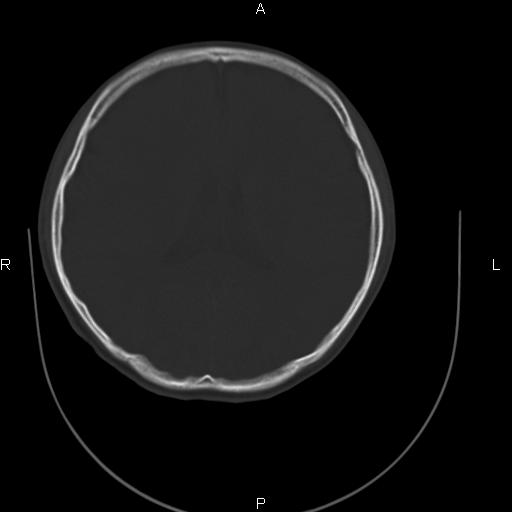

标题: CT27115:大家看一看,这孩子的颅骨表现?

两名中学生打架,脑质内未见异常,未上传。

两例——颅骨结构正常,未见明显骨折征象。

感觉第2个颅缝密度高,额顶部板障有点厚,正常变异?地中海贫血?